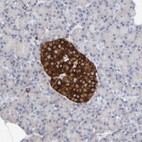

Immunohistochemical staining of human Cerebral cortex shows strong positivity in neuropil.